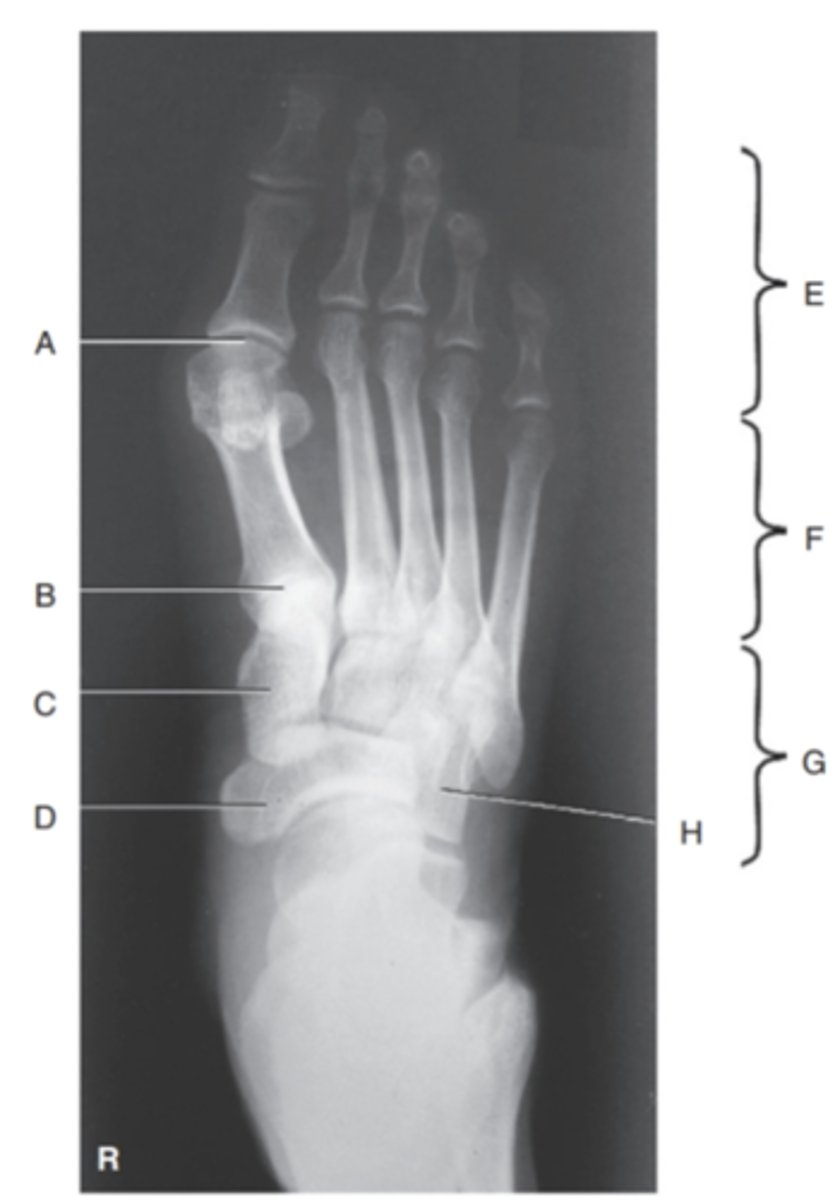

(AP AXIAL FOOT) what is A?

First metatarsophalangealjoint

what is B?

First tarsometatarsal joint

what is C?

Medial cuneiform

what is D?

Navicular

what is E?

phalanges

what is F?

metatarsals

what is G?

tarsals

what is H?

cuboids